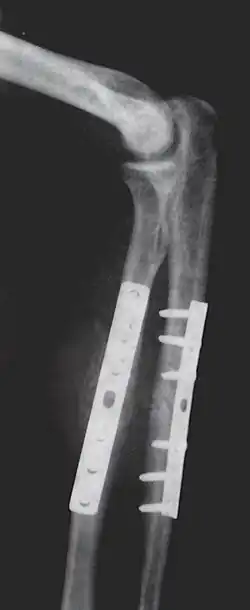

Internal fixation is an operation in orthopedics that involves the surgical implementation of implants for the purpose of repairing a bone, a concept that dates to the mid-nineteenth century and was made applicable for routine treatment in the mid-twentieth century.[1] An internal fixator may be made of stainless steel, titanium alloy,[2] or cobalt-chrome alloy.[3]

Open reduction internal fixation (ORIF) involves the implementation of implants to guide the healing process of a bone, as well as the open reduction, or setting, of the bone. Open reduction refers to open surgery to set bones, as is necessary for some fractures. Internal fixation refers to fixation of screws and/or plates, intramedullary rods and other devices to enable or facilitate healing. Rigid fixation prevents micro-motion across lines of fracture to enable healing and prevent infection, which happens when implants such as plates (e.g. dynamic compression plate) are used. ORIF techniques often are used in cases involving serious fractures such as comminuted or displaced fractures or, in cases where the bone otherwise would not heal correctly with casting or splinting alone.

Closed reduction internal fixation (CRIF) is reduction without any open surgery, followed by internal fixation. It appears to be an acceptable alternative in unstable distressed lateral condylar fractures of the humerus in children, but if fracture displacement after closed reduction exceeds 2 mm, open reduction and internal fixation is recommended.[4]